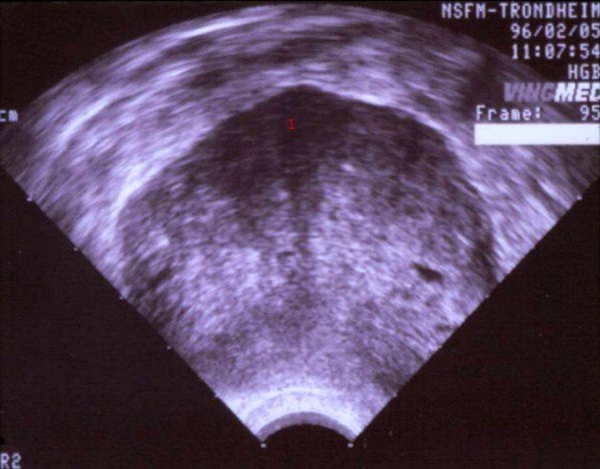

Ultralydsskanning af solid svulst i æggestok

Ultralydsskanning af æggestok med solid svulst (tumor).